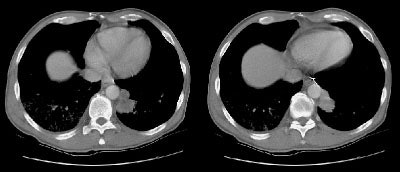

Example of the normal hilar interstitium: The images below are from a patient without bronchogenic carcinoma. The images demonstrate normal hilar lymphatic tissue (yellow arrow right image) which appears as a low density region between the bronchus and pulmonary vessel. A small calcified node is seen on the right (red arrow) in this patient with prior granulomatous disease. NOTE: Click image to enlarge.